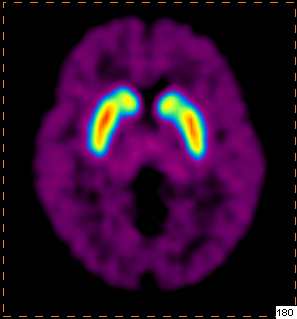

我科使用11C-CFT进行脑部多巴胺受体显像

PET/CT示:

双侧尾状核、双侧壳核放射性摄取对称,未见明显减低

根据PET图像,最终排除帕金森病